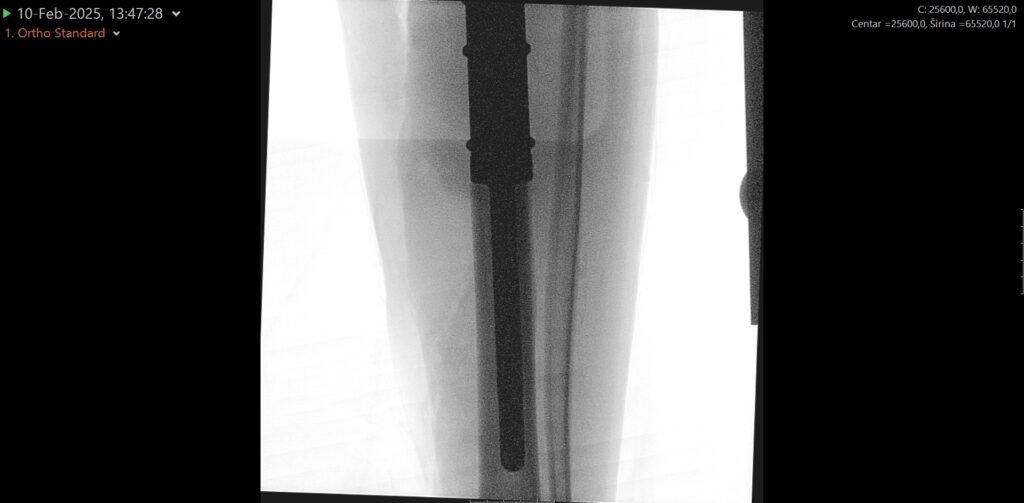

No to više nije potrebno jer je zahvat uspješno obavljen u splitskoj bolnici, i to baš mladom Splićaninu, koji se dobro oporavlja. Tijekom zahvata u potpunosti mu je odstranjen koljenski zglob te gornjih 17 cm goljenične kosti koji su zamijenjeni posebnom tumorskom protezom i nadomjestkom – implantatom za odstranjenu kost. Potom je nastali defekt primarno zatvoren i pokriven kožno-mišićnim režnjem.

Zahvat je obavio tim Zavoda za ortopediju i traumatologiju, uz vodstvo posebnog gosta dr. Marka Bergovca, predstojnika Klinike za ortopediju i traumatologiju Klinike Diakonissen iz Schladminga i vodećeg stručnjaka u području rekonstruktivne i tumorske ortopedske kirurgije. Djelatnici Zavoda za ortopediju i traumatologiju izrazito su zadovoljni što su im pacijent i njegova obitelj poklonili povjerenje kako bi se ovaj složen i zahtjevan zahvat obavio upravo u KBC Split umjesto odlaska u neku od inozemnih klinika.